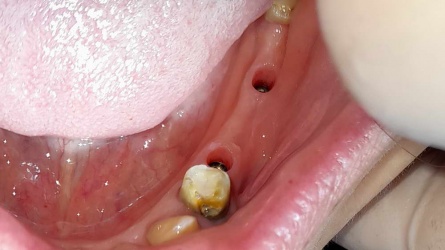

زراعه الاسنان كما تبدو بعد ازاله مشكلات اللثه

فم المراجعه قبل البدء بالعلاج وبعد التركيب مشكلات اللثه